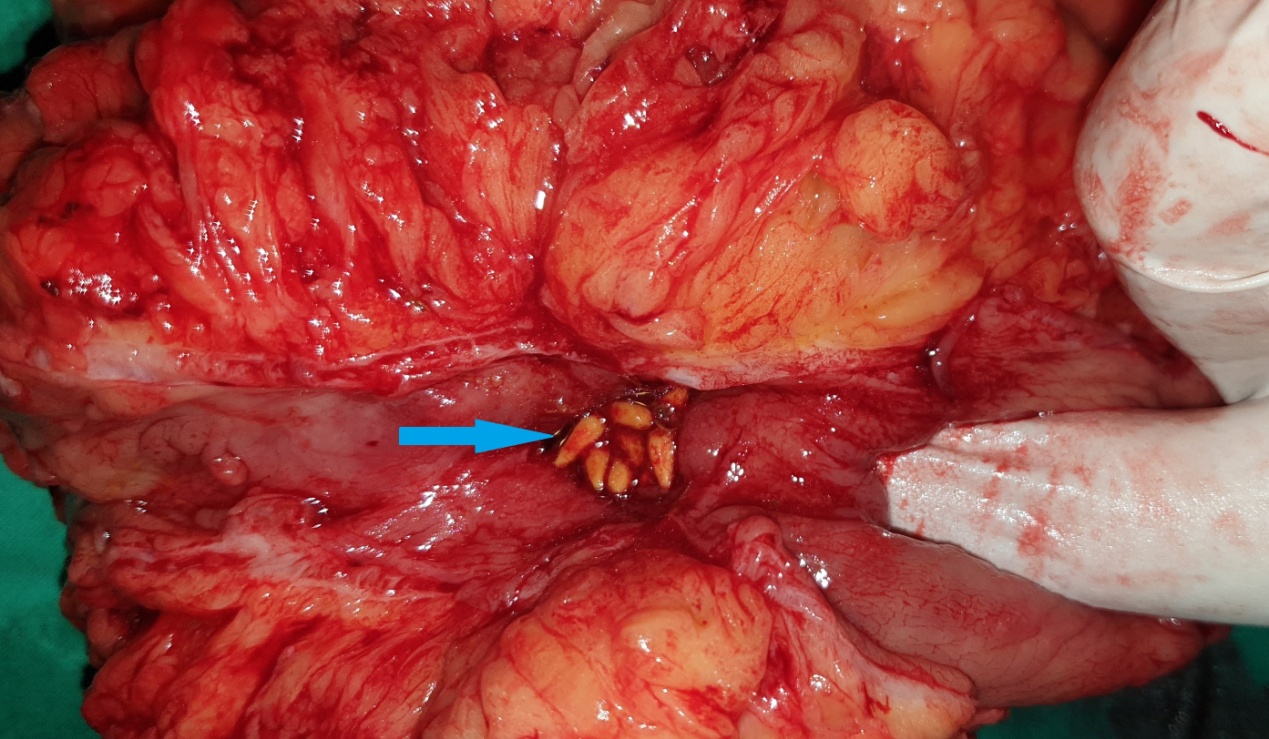

Anatomical forceps within the fistula orifice in the duodenum (Courtesy Dr. V. Penopoulos)